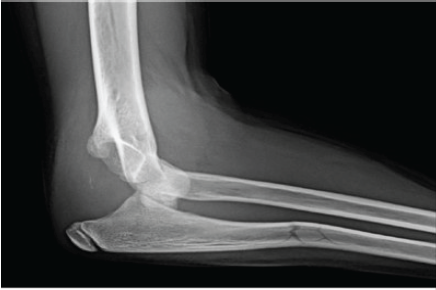

Elbow Dislocation Associated with Severely Displaced Radial Neck Fracture and Ulnar Diaphyseal Fracture in an 11-Year-Old Girl – A Very Rare Case Report

Louis Biernaux , Valentina Maestri , Manon Deguée , Pierre-Louis Docquier

………………………………p.235-238